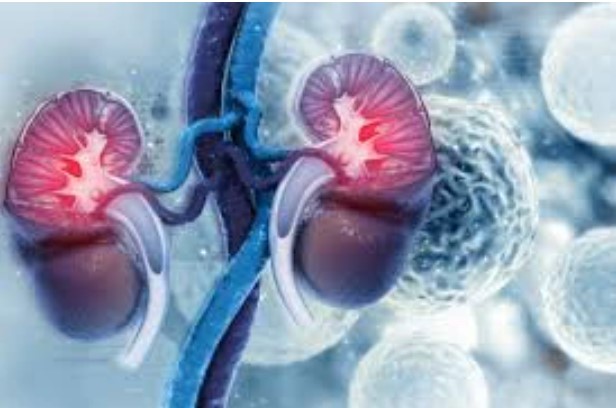

The urinary organ may be a crucial organ within the body that aids in the elimination of waste in the variety of urine. The blood is additionally filtered by the kidneys before being came to the heart.

Chronic kidney disease, kidney failure, kidney stones, glomerulonephritis, acute nephritis, polycystic kidney disease, tract infections, uremia, hydronephrosis, kidney cysts, and different disorders will all injury the kidney…Click Here To Continue Reading>> …Click Here To Continue Reading>>